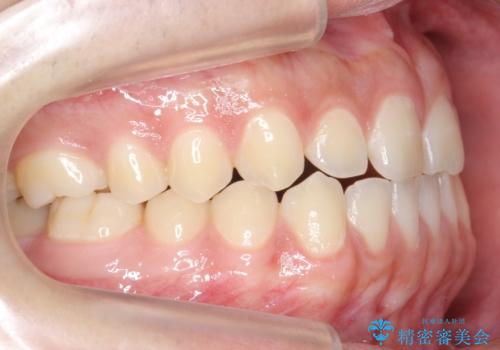

前歯のすきま 受け口 インビザラインで

- 前歯のすき間を気にして来院。

受け口もあり、前歯が端同士であたる、切端咬合となっていました。

下の歯のすき間を閉じて上の歯の内側に入るように位置付けました。

上の前歯は下の歯と直接へりが当たっていた状態(切端咬合)だったため、形がいびつだったのは、わずかにやすりがけをして整えました。

セラミックですき間を閉じようとすると、すきまをうめるために巨大な歯になり、また、下の歯が前に出て強く当たるため、セラミックがかけるおそれがあります。また、下の歯をさけようとすると角度をかえるために歯を極端に削らなければならなくなり、神経をとらなければいけなくなるリスクもあります。

このような歯並びは、セラミックでかぶせるよりは、矯正治療の

適応と言えます。